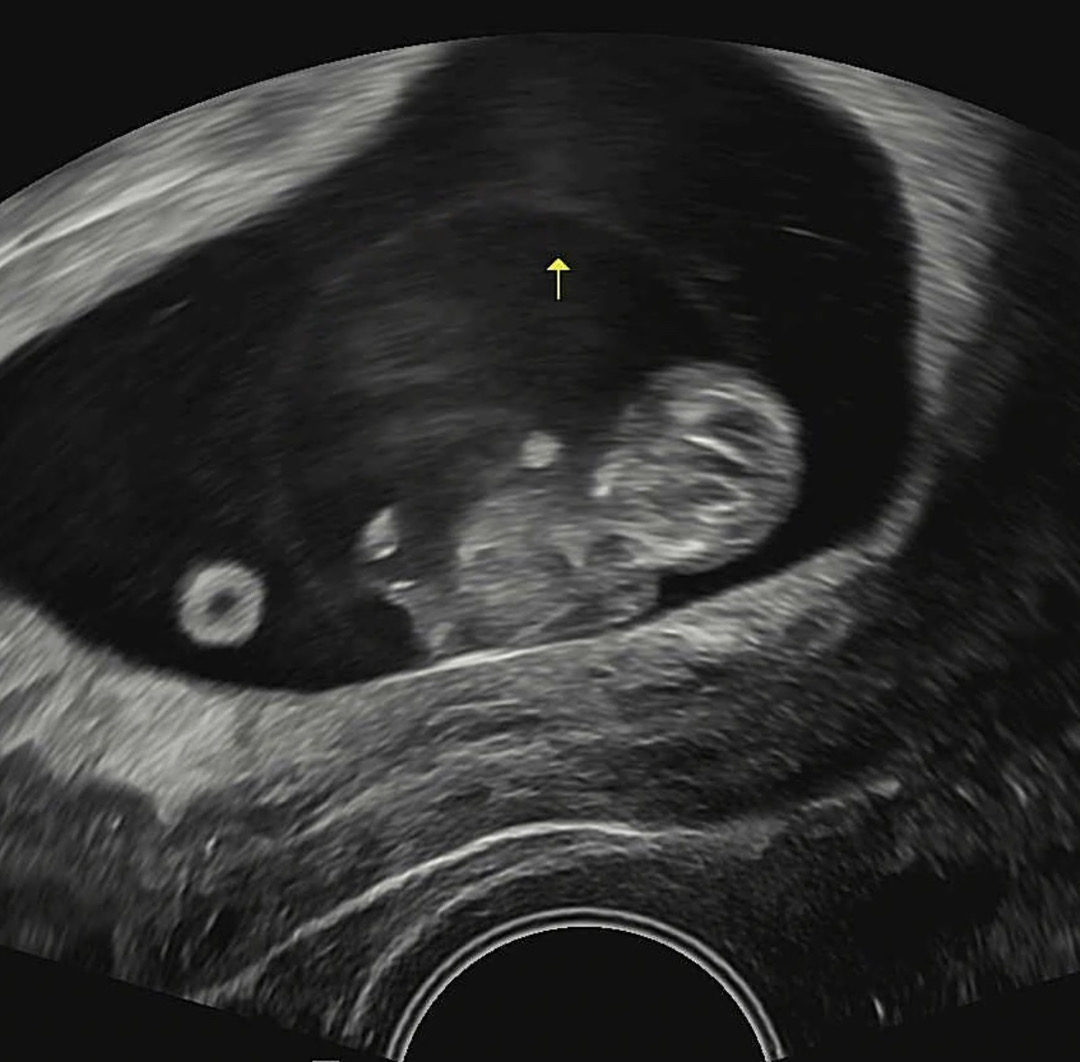

9주2일차 젤리곰 보고 왔어용🧸 꿈틀꿈틀 꼬물꼬물 거리는데 너무 귀엽더라구여!! 입덧이 딱히 없어 증상이 없으니 애기가 잘 있나 걱정했는데 아주 무럭무럭 자랐네요>,< ㅎㅎㅎㅎ 다음 1차 기형아검사때까지 잘 자라길🍀🍀